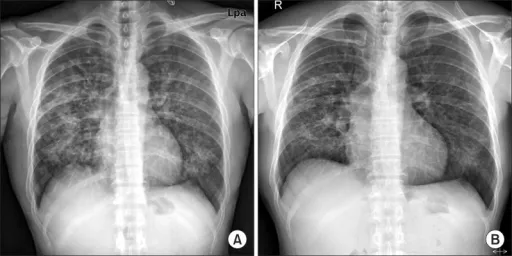

- Auscultation: Often unremarkable, despite significant X-ray findings (wheezes, rhonchi).

- "Walking Pneumonia": Patients often remain ambulatory and appear less ill than their chest X-ray suggests.